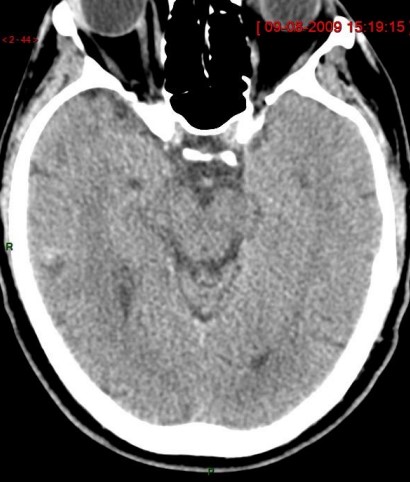

"Cachez ces anévrismes que je ne saurais voir"